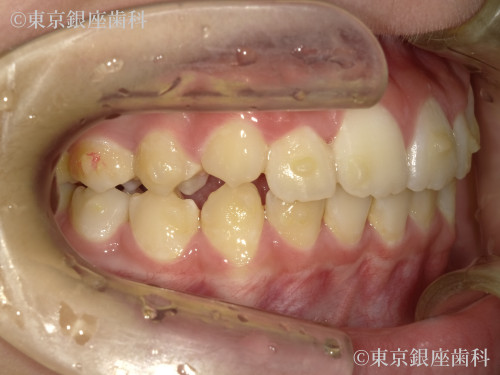

Before

10代 女性

治療期間 11ヶ月 費用 65万円(税込)

インビザライン:ファースト